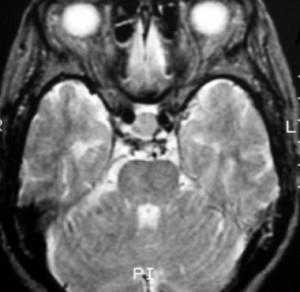

На этом Т2-взвешенном изображении она изоинтенсивна спинно-мозговой жидкости.

![f7]()

Крупная гиперинтенсивна по сравнению со спинно-мозговой жидкостью на аксиальном протонно-взвешенном изображении. Отмечается расширение турецкого седла с латеральным отклонением чуть заслоненной, но проходимой кавернозной частью внутренней сонной артерии.